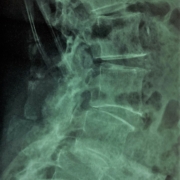

1. Alleviare il Dolore alla Schiena e al Collo

Uno dei motivi principali per cui le persone si rivolgono a un chiropratico è il trattamento dei dolori alla schiena e al collo. La chiropratica si concentra sulla colonna vertebrale, e molte persone trovano sollievo da fastidi cronici come il mal di schiena, il dolore cervicale e la rigidità grazie a manovre specifiche e mirate. Un chiropratico esperto può correggere gli allineamenti vertebrali, riducendo il dolore e migliorando la mobilità.

5. Trattamento della Sciatica e dell’ernia del disco lombare

La sciatica, un dolore che si irradia lungo il nervo sciatico, è un disturbo comune che può causare dolore intenso e formicolio nelle gambe e nella parte bassa della schiena. Un chiropratico laureato è in grado di trattare la sciatica correggendo eventuali disallineamenti nella colonna vertebrale, alleviando così la pressione sul nervo sciatico e riducendo il dolore. Il Dr Clementoni ha condotto una ricerca clinica già approvata con delibera di Regione Lombardia su mal di schiena lombare con

o senza sciatica in presenza di ernia del disco o protrusione, presentata al congresso mondiale sul mal di schiena (Dubai 2013). Oltre l’85% delle persone che hanno seguito il ciclo di trattamento con il Dr Clementoni ha riscontrato:

– eliminazione o rilevante riduzione di mal di schiena e dolore alla gamba (sciatica);

– migliorata capacità di svolgere le attività quotidiane;

– sostanziale eliminazione dei farmaci steroidei (cortisone) e antinfiammatori;

– riduzione del rischio di intervento chirurgico per ernia del disco.